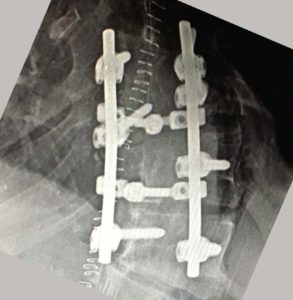

- α

- β

Εικόνα 4 (α,β)

Α. Απλή Ακτινογραφία Σ.Σ. : Μετωπιαία και πλαγία σε όρθια στάση: Το αριστερό θωρακο-οσφυϊκό κύρτωμα είναι 71ο.